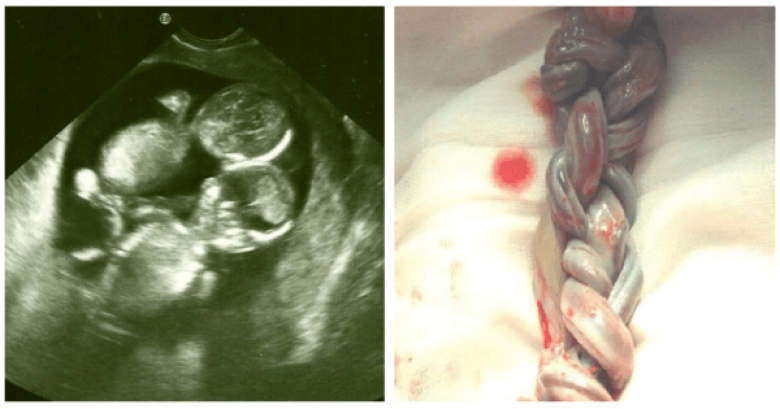

Настало время для первого УЗИ. Кейт, переполненная материнских чувств, абсолютно счастливая, отправилась к доктору. Уже давно знакомый для ее семьи медик шутит: «Может у тебя там снова двойня?» Как в воду глядел! В утробе Кейт действительно билось два сердца. Но эта новость, к сожалению, была не единственной на тот день.

Эмбрионы разделились только после 8-13 дней осеменения. Это означало, что между двумя детьми не было защитной мембраны. Через пару дней дети могли бы стать сиамскими близнецами. Но это еще полбеды! При подобной монохориальной беременности пуповина одного ребенка могла запутаться о другого, вызывая риск удушения малыша. Шанс на жизнь у этих близнецов не составлял больших процентов.

Врач советует Кейт не беспокоиться, держать все в секрете и позволить природе взять верх… Но какая мать смогла бы так поступить? После двадцати восьми недель беременности эта женщина проводит тридцать пять дней в больнице, сражаясь каждый миг за жизнь своих малышей. При родах ей делают кесарево сечение. Когда доктора увидели пуповину, в комнате воцарилась мертвая тишина.

Обе пуповины были плотно переплетены, как косичка! Трудно было поверить в то, что девочки выжили. Но это еще далеко не все.

Близнецы родились недоношенными, очень маленькими и слабыми, но, слава Богу, абсолютно здоровыми! Доктора выбрали нужный момент. Если бы они подождали еще несколько часов, спутанные пуповины лишили бы девочек всякого шанса на жизнь.